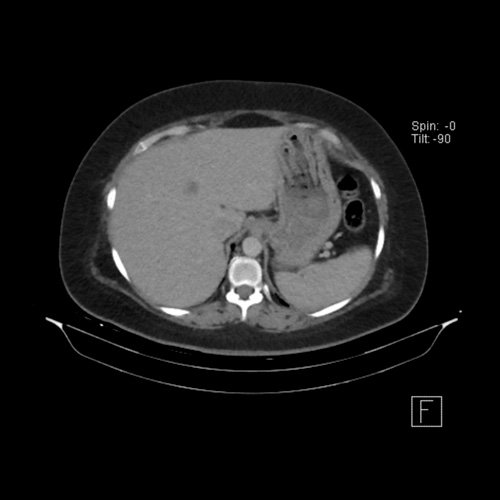

• Tomografía de abdomen y pelvis sin contraste oral con contraste EV (12/02/26):  El hígado es de forma, tamaño y situación habituales. Su superficie es lisa, y sus bordes son agudos. Imagen hipovascular aislada de 15 mm en segmento V de aspecto inespecífico. Sugiero complementar con RMI. La vía biliar intra y extrahepática es de calibre conservado. La vesícula biliar es de forma, tamaño y situación normales, sin imágenes que sugieran la presencia de litiasis. Tener en cuenta que este método puede pasar por alto litiasis colesterínicas. El bazo es de forma, tamaño y situación normales. El páncreas es de características normales. El conducto de Wirsung es de calibre conservado. Adenoma adrenal izquierdo de 16 mm. Ambos riñones son de forma, tamaño y situación habituales. Concentran y eliminan adecuadamente la sustancia de contraste. Sin evidencia de alteraciones calicopiélicas ni ureterales. La aorta, las arterias ilíacas primitivas, internas, externas y femorales, son de calibre y trayecto conservado, permeables. La vena cava inferior y las venas ilíacas primitivas, internas, externas y femorales son de calibre y trayectoria conservados, permeables. No se observan adenomegalias intraperitoneales, retroperitoneales, ilíacas ni inguinales. No se observan alteraciones a nivel del tracto gastrointestinal. La vejiga es de paredes lisas, sin presentar efectos de masa endoluminales ni parietales. Utero en AVF, lateralizado a izquierda. Pequeña hernia umbilical de contenido graso y escaso líquido intrasacro. No se identifican alteraciones en las estructuras óseas visualizadas.

TC de abdomen y pelvis con contraste endovenoso (12/02/2026) Corte axial: hígado de forma, tamaño y situación habituales, con superficie lisa y bordes agudos.  Imagen hipovascular aislada de 15 mm en segmento V de aspecto inespecífico.

TC de abdomen y pelvis con contraste endovenoso (12/02/2026) Corte coronal: hígado de forma, tamaño y situación habituales, con superficie lisa y bordes agudos.  Imagen hipovascular aislada de 15 mm en segmento V de aspecto inespecífico.

TC de abdomen y pelvis con contraste endovenoso (12/02/2026) Corte sagital: hígado de forma, tamaño y situación habituales, con superficie lisa y bordes agudos.  Imagen hipovascular aislada de 15 mm en segmento V de aspecto inespecífico.